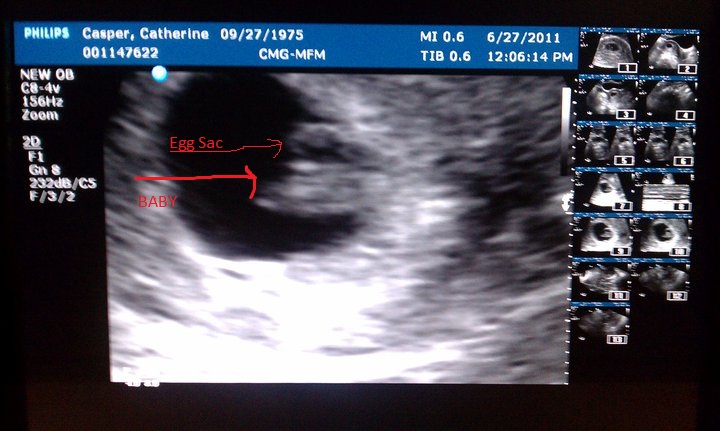

Wes and I are expecting our second baby. All my blood work up came back today as excellent. And I had an ultrasound this past Monday. Baby is progressing, perfectly. I was able to see the heart beating on the monitor and it was amazing! 152 beats a minute. Very strong and healthy! I just wish the stomach sickies would end and my vertigo would go away. Other then that, it's been okay. LOL

Due on Feb. 14th, 2012. Yes, Valentine's Day!